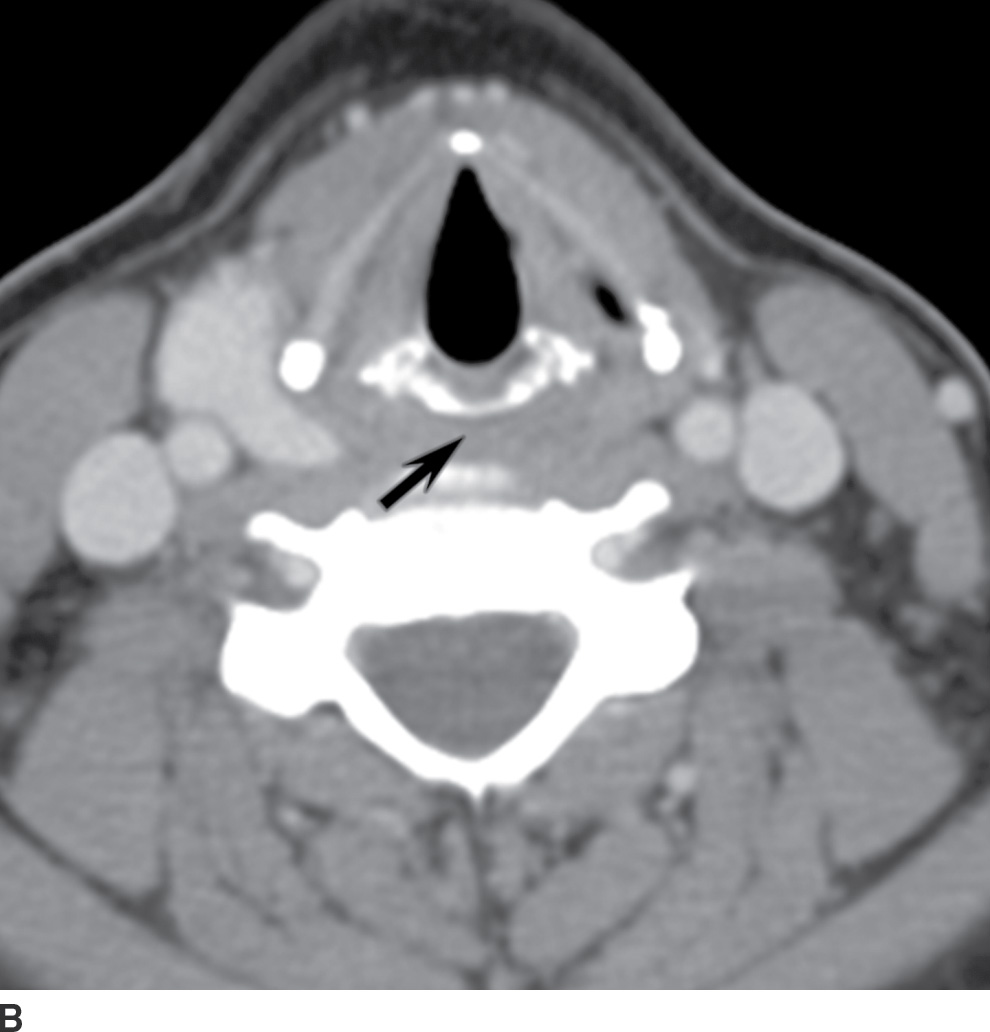

From radiologykey.com

Mucosal Cancers Neck Primaries and the Lymph Nodes Radiology Key Spine Cancer Neck Learning that you have a spinal tumor can be overwhelming. Some of the cancers that may involve the spine. Spinal metastasis (metastatic spinal cancer) happens when cancer in another part of your body spreads ( metastasizes) to. S pinal tumors can involve the neck, back and lower back. A spinal tumor is an abnormal growth of cells within or surrounding. Spine Cancer Neck.

Mucosal Cancers Neck Primaries and the Lymph Nodes Radiology Key Spine Cancer Neck A spinal cord tumor, also called an intradural tumor, is a spinal tumor that that begins within the spinal cord or the covering of the spinal cord (dura). Learning that you have a spinal tumor can be overwhelming. But you can take steps to cope after your diagnosis. A spinal tumor is an abnormal growth of cells within or surrounding. Spine Cancer Neck.

Mucosal Cancers Neck Primaries and the Lymph Nodes Radiology Key Spine Cancer Neck Most spinal cancer occurs inside the spinal column and usually doesn’t affect the spinal cord. A spinal cord tumor, also called an intradural tumor, is a spinal tumor that that begins within the spinal cord or the covering of the spinal cord (dura). Learning that you have a spinal tumor can be overwhelming. Some of the cancers that may involve. Spine Cancer Neck.